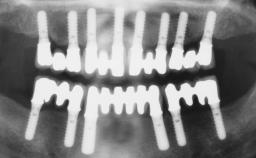

Jean-Pierre Bernard

Genève, Switzerland